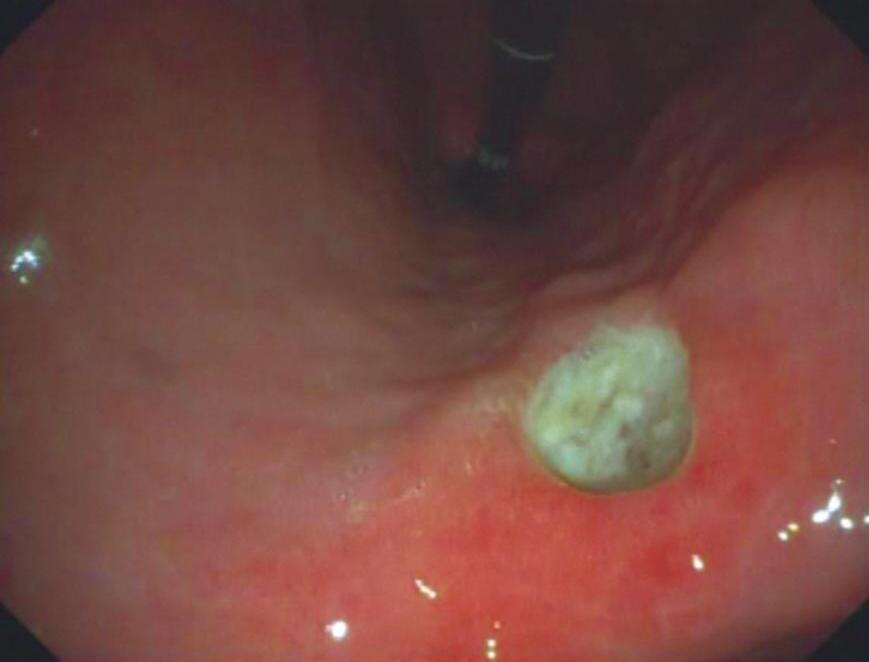

2. Paciente do sexo masculino, 20 anos de idade, previamente hígido, procura atendimento com queixa de disfagia importante de início súbito há 2 dias, referindo dor retroesternal e dificuldade até para engolir saliva. Nega febre, tosse ou sintomas respiratórios. Relata uso recente de um comprimido de anti-inflamatório não esteroide (AINE) para dor muscular, ingerido sem água e imediatamente antes de deitar. Foi submetido à endoscopia digestiva alta (EDA), cujo achado está demonstrado na Figura 4.2. Qual o diagnóstico mais provável e a conduta inicial recomendada?

Figura 4.2 (A e B) Endoscopia digestiva alta mostrando úlceras esofágicas em paredes opostas, chamadas kissing ulcers

Fonte: imagem pertencente à Dra. Caroline Tatim Saad.

2. Resposta C

O quadro clínico típico de esofagite medicamentosa inclui dor retroesternal e disfagia após ingestão de certos medicamentos sem água e/ou em posição supina. A endoscopia revela úlceras lineares em paredes opostas, chamadas kissing ulcers no esôfago médio, geralmente onde o comprimido permanece impactado. A conduta inclui suspensão do fármaco, uso de inibidores da bomba de prótons (IBP) e orientação para ingestão dos comprimidos com pelo menos 200mL de água, em posição ereta e evitando deitar-se logo após. Ao se prescrever qualquer medicamento, muitas vezes não é lembrado de dar as orientações sobre como o paciente deve ingerir, da importância da posição corporal, jejum ou não, ingestão de líquidos, higiene da boca (como no caso dos corticoides inalatórios para asma), por ser situação habitual para os médicos. Porém, essa informação não é de conhecimento de grande parte da população e pode prevenir uma série de complicações relacionadas à forma de administração de medicamentos.